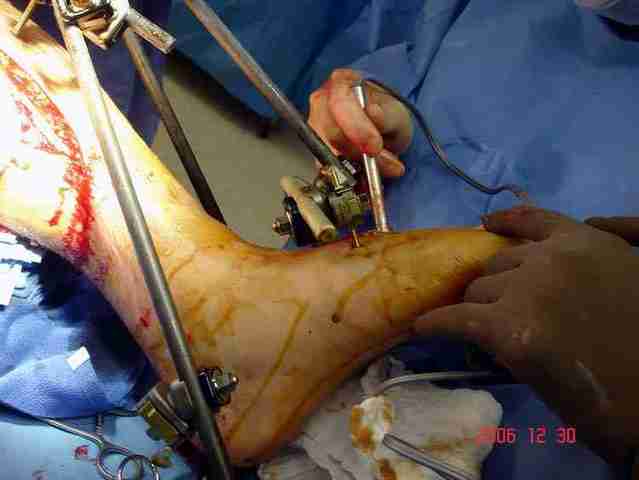

Срочная фасциотомия на всех 4 компартментах: латерально и медиально,

кстати было достаточно только латеральной фасциотомии, чтобы услышать на допплере пульсацию,

на бедре измерения не подтвердили подозрения на компартмент синдром и рана была закрыта вакуумной губкой (wound VAC).

В настоящее время больной в реанимации по поводу Черепно Мозговой Травмы и состояние улучшается. Запланировал ушивание раны в пятницу, если позволит состояние мягких тканей и при отсутстви отека возможно удастся просунуть перкутанномедиальную пластину.